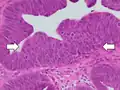

Histopathology of high-grade dysplasia in a tubulovillous adenoma, in this case seen mainly as loss of cell polarity, as cells become more plump and haphazard than the elongated and parallel nuclei of surrounding low-grade dysplasia.